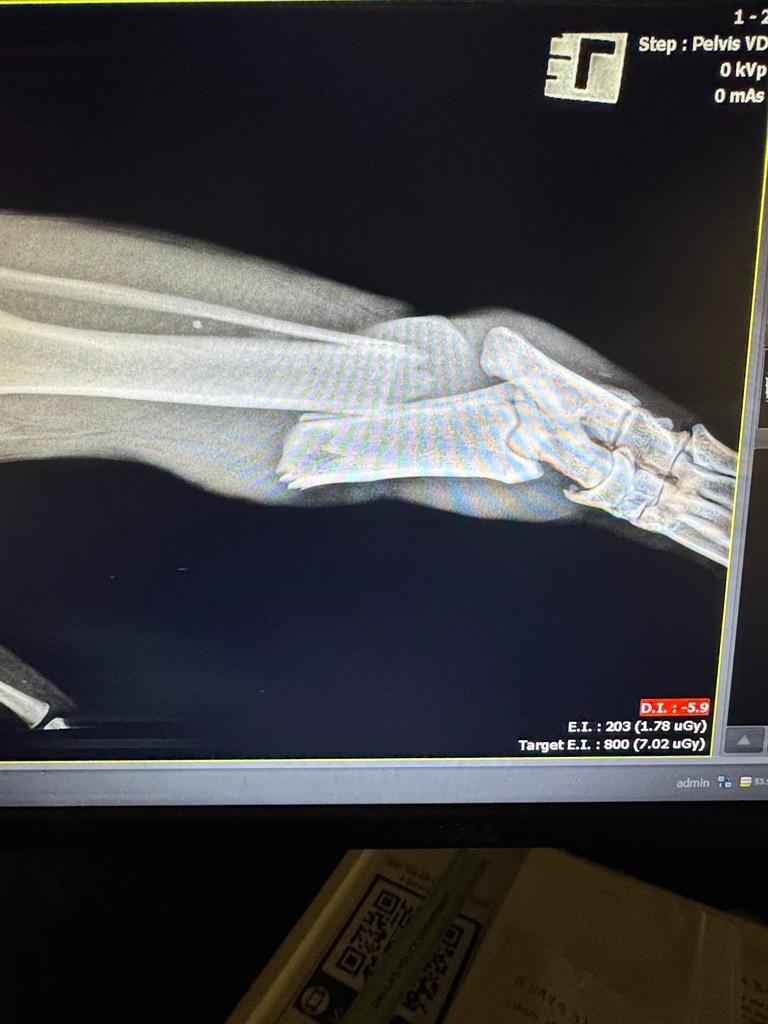

Meet Queen my new foster. She is a 70 pound, 3-year-old stray great Pyrenees from Dallas, TX. She was found after being hit by a car with puncture wounds from a dog attack and a pretty bad fracture. I am not rich. I am a mother of two boys and a pet parent. But I can't let this dog be euthanized and Dallas animal services can only do so much. This dog either needs surgery or will lose her leg. Please help me afford the veterinary cost of saving her leg or if it is in her best interest, having it amputated. I will give her a home and somewhere safe with food and other dogs to love on. I know this dog is meant for someone and it is a miracle from God that she is alive. I intend to help her get to the next place and her forever family but I need help from my community to do this.